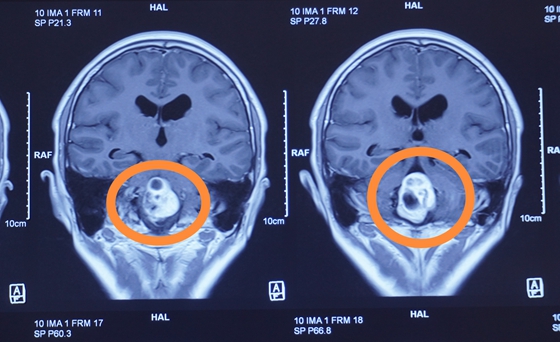

入院后,患者完善检查后发现病情异常凶险:在主管人体呼吸、心跳和运动的延髓处的血管母细胞瘤,手术治疗的难度和风险都很大。

7月26日,经过充分术前准备,袁贤瑞教授团队在全麻插管下为患者行脑干肿瘤切除术。术中显微镜下“Y”形剪开硬膜,见肿瘤位于延髓背侧、四脑室内。质地中等,血供较丰富,边界清楚,色灰红。先仔细分离肿瘤边界,可见小脑后下动脉分支供血,凝断供血动脉,分块切除肿瘤,肿瘤全切,手术过程顺利。术后病理结果示:血管母细胞瘤。

延髓主管人体的呼吸心跳,脊髓主管人体的运动。这些部位作为人体的生命中枢,一旦发生病变,将直接危及患者生命。此例延髓实质性血管母细胞瘤非常罕见,治疗过程对于医疗团队的手术技术、治疗理念乃至护理水平都是一场大考,湘雅常德医院神经外科这次救治中,交出了一份满意的答卷。